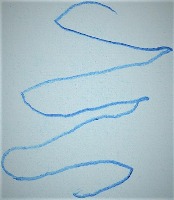

Parkinson's Disease Early Detection: This model can be used in telemedicine and eHealth applications to analyze drawings or handwriting samples drawn by patients. Early diagnosis of Parkinson's Disease can help in beginning the treatment early and slow down the progression of the disease.

Medical Research: Researchers studying Parkinson’s Disease can use this model to analyze large sets of drawings or handwritings, identifying trends and correlations between identified Parkinson’s Disease positive cases and the characteristics of their drawing.

Home Monitoring System: This model can be incorporated into a home monitoring system where elderly individuals or at-risk populations can regularly submit handwriting or drawing samples. These can be analyzed for Parkinson's symptoms, enabling early intervention and care.

Rehabilitation: For those patients already diagnosed with Parkinson's Disease, this model can help monitor the progression of their disease based on regular analysis of their handwriting or drawings. This would facilitate tailoring their treatment and rehabilitation program based on their current status.

Pharmaceutical Industry: Drug companies can use this model in clinical trials to monitor the impact of new Parkinson's Disease drugs on patients. This can provide valuable data on the effectiveness of the drugs, based on whether they help improve the drawing and handwriting symptoms associated with Parkinson's.